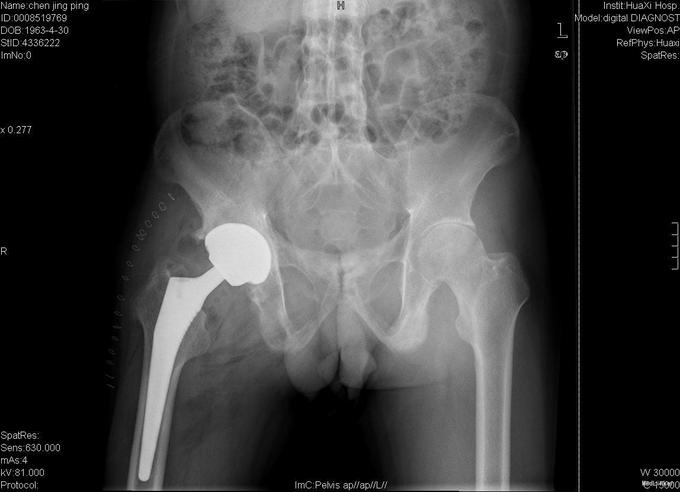

诊断:强直性脊柱炎 右髋关节强直 治疗:完善相关检查后在全麻下行右侧全髋关节置换术+髋臼成形术,手术顺利,术后予以抗炎+抗凝+阵痛等治疗。

术后患者恢复良好,右髋屈曲100°,伸直0°,外展40° 1、强直性脊柱炎起病特点有哪些 2、实验室检查及影像学表现有何特点? 3、治疗原则及主要治疗方法有哪些?